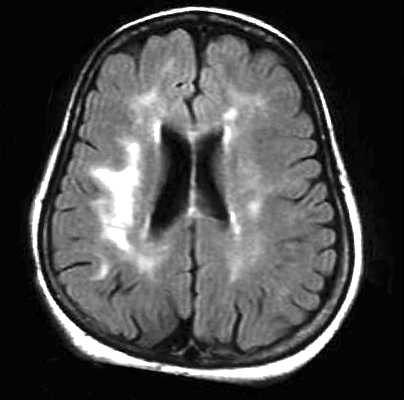

脑白质疏松症(Leukoaraiosis,LA)是在1987年加拿大神经学家Hachinski提出,leukoaraiosis这一名词由希腊文“leuko”(意为“白色”)和“araiosis”(意为“稀疏”)组成。脑白质疏松症是多种不同病因引起的一组以脑室周围及半卵圆中心区脑白质的弥漫性斑点状或斑片状双侧对称性缺血改变为主的临床综合征,这些改变在CT上为低密度,在MRI图像上为高信号的区域。

脑白质疏松症的发展有一定的模式,初期我们可以观察到脑室周围病变朝侧脑室边缘发展(如下图1),当问题加重时则呈现图2。